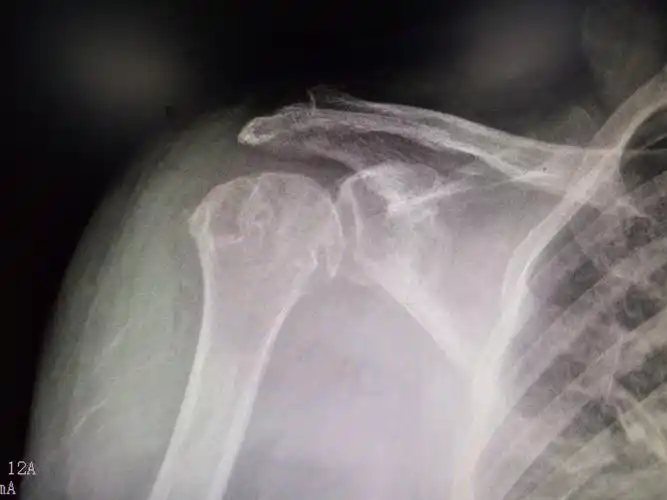

肩关节半脱位

患侧上肢向下脱垂,使得韧带松弛上部从关节处下滑,出现肩关节半脱位.